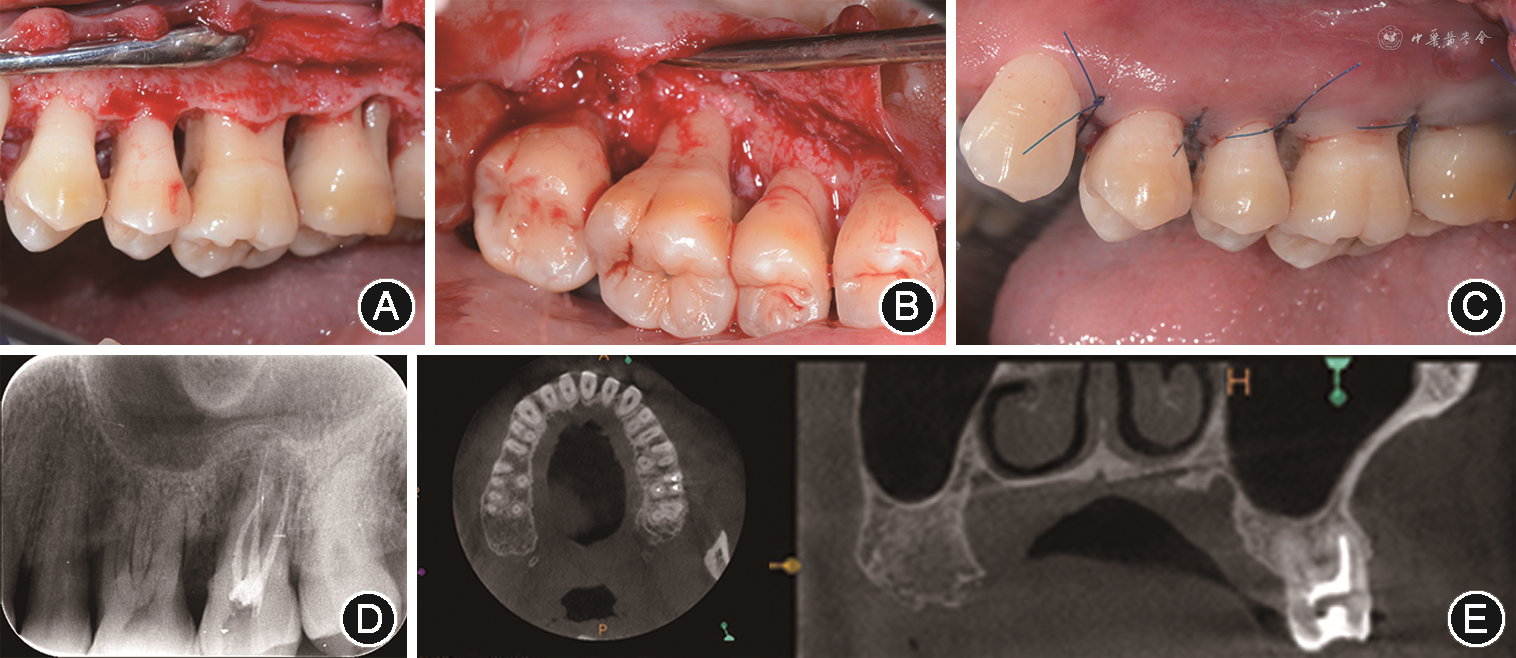

2.临床检查:口腔卫生较差,牙石指数为2,菌斑指数为2,牙龈红肿明显,质地软,探诊出血指数均为4。27探诊深度6~9 mm,附着丧失6~7 mm,根分叉病变2度,松动Ⅰ度,牙冠完整,未见明显龋坏及隐裂,叩痛(-),颊侧正中龈缘下5 mm处可见窦道,探至根尖处,牙髓冷测试无反应,电活力测试值80,27影像学检查显示:牙槽骨位于根中1/3处,根尖处可见直径约8 mm的低密度影,根分叉区密度降低。36缺失。前牙及其余磨牙探诊深度6~8 mm,可及附着丧失4~6 mm,17松动2度,18、46、47松动Ⅰ度。个别位点有溢脓。前牙及其余磨牙影像学检查显示:16、26和46牙槽骨角形吸收至根中1/3处,前牙水平吸收至根中1/3处;其余牙齿牙槽骨水平吸收至根颈部1/3处,骨硬板不连续。前牙散在间隙,上前牙扇形移位,上颌前突。初诊时临床及影像学检查见图1。

像;F:左后牙

像;G:右下后牙舌侧;H:下前牙舌侧;I:左下后牙舌侧;J:曲面体层X线片;K:27颊侧观显示颊侧窦道;L:27根尖片示牙槽骨位于根中1/3处,根尖处可见直径约8 mm低密度影,根分叉区密度降低

像;G:右下后牙舌侧;H:下前牙舌侧;I:左下后牙舌侧;J:曲面体层X线片;K:27颊侧观显示颊侧窦道;L:27根尖片示牙槽骨位于根中1/3处,根尖处可见直径约8 mm低密度影,根分叉区密度降低3.诊断及治疗计划

(2)第2阶段:2017年8月至2018年3月行牙周手术治疗。于右上、左上、右下及左下4个区段进行4次牙周手术,每次间隔1个月左右。右上、左上及左下行牙周翻瓣术及骨成形术,右下区段行牙周翻瓣术及46植骨术。左上区段牙周手术前27颊侧窦道仍可见,术中使用手工和超声刮治器彻底清创,可见牙槽骨吸收为水平型,因此进行骨成形术。在牙周翻瓣术后3个月复查时可见窦道完全闭合,探诊深度降至4 mm及以下,术后1年影像学检查显示根尖病变及根分叉病变愈合(图2)。右下区段进行牙周翻瓣术和46植骨术,术中清创后可见近远中2~3壁骨下袋,远中骨袋深5.0 mm,近中骨袋深2.5 mm,骨袋近远中向宽度为3.0 mm,颊侧釉质牙骨质界距离骨嵴顶3.0 mm,舌侧釉质牙骨质界距离骨嵴顶5.0 mm,近远中骨袋中植入植骨材料(Bio-Oss,Geistlich,瑞士)和浓缩生长因子(concentrated growth factors,CGF)膜(Medifuge,Salfident,意大利)。牙龈瓣冠向复位,改良褥式缝合及间断缝合关闭创面。术后1~2周复查显示牙龈组织愈合良好,未见伤口裂开。46植骨术后1年可见牙龈色粉,质地韧,探诊深度3~4 mm。影像学检查可见角形吸收处牙槽骨密度增加,骨硬板形成且连续。治疗疗程为7个月。4次手术后6个月复查,牙周检查大表显示所有位点探诊深度均≤5 mm,探诊出血阳性位点百分比<30%。